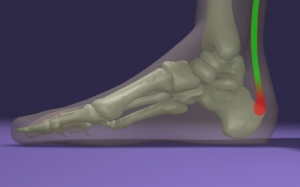

Achilles ín fájdalmaAchilles tendinítis - BNO:M7660

Az Achilles innak a sarokcsonti tapadási helyén és efelett 1-2 cm-re sokszor erős fájdalom jelzi a rendszerint sport tevékenység végzésének túlerőltetettségét.

Eleinte ezt az ujj vastagságú inat körülvevő hártya gyullad be, majd további erőltetés hatására a gyulladás átterjed az ínra, de leggyakrabban az ín tapadási helyére. A gyulladást a fájdalom mellett bőrpír, esetleg a terület duzzanata jelzi. A fájdalom reggel, felkeléskor erősebb, reggeli séta és gyenge bemelegítés közben enyhül, majd edzés közben erősödik majd mozgás közben ismét gyengül.